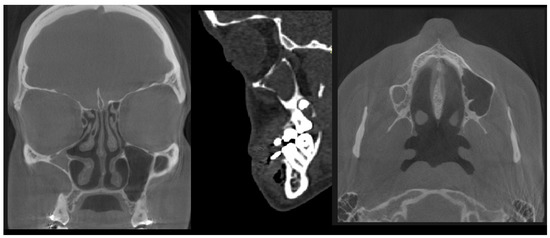

- (7)

- Type 7 MSH = maxillary sinus hypoplasia (Figure 10 and Figure 11)—a very rare, probably somehow atypical case of complete symmetrical MS retraction and atrophy, without CRS. Possible relation to bilateral MSH—bilateral maxillary sinus hypoplasia should be considered and requires further studies [33].